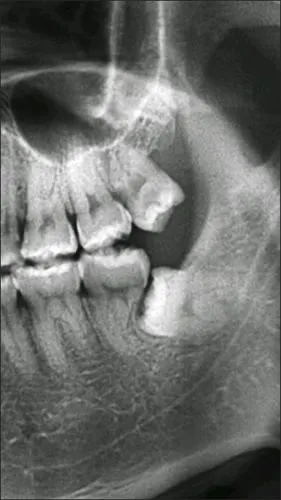

第二磨牙还能保得住吗?

下颌第一磨牙解剖图